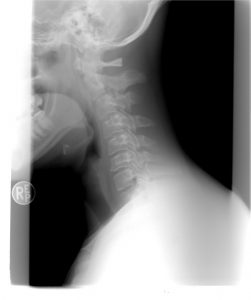

Wiele osób ma problemy z odcinkiem szyjnym i karku, który wywołuje ból. Dzisiaj pokażemy Ci jak w prosty sposób przy pomocy ćwiczeń Rolanda Brachta uwolnić się od napięcia mięśniowego. Nie ma sensu niepotrzebnie cierpieć, jeśli na wyciągnięcie ręki jest prosta metoda, która przyniesie ulgę.